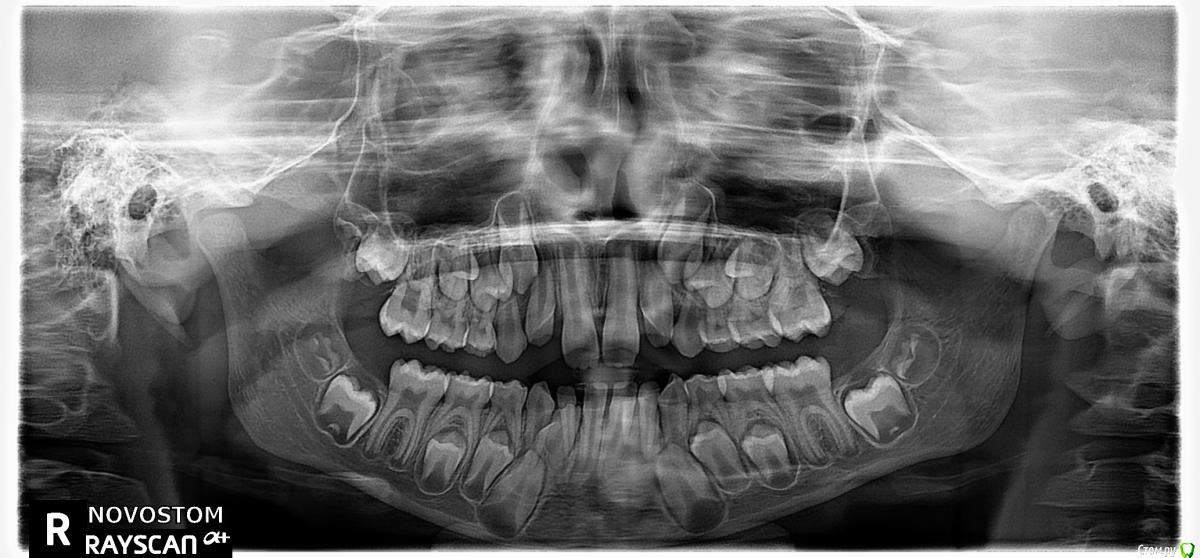

face Опубликовано 28 сентября, 2018 Поделиться Опубликовано 28 сентября, 2018 (изменено) Добрый день. Ребенок 10 лет. Обратились к врачу ортодонту (№1). Сделали снимок Ортопантомограмму, врач расшифровал и дал рекомендацию по подрезке уздечки, затем брекеты. Мы решили обратиться к другому специалисту (№2) спустя месяц, в то же время у ребенка появился на нижней челюсти зуб непонятного происхождения ( все снимки будут ниже, на снимке этот зуб обведен черным кружочком). Этот же специалист (№2), призвав еще одного стоматолога на помощь ( типа, может, заработался), а тот подтвердил, что снимок не соответсвует тому, что во рту у ребенка- зуб пробивается слева, а слева на снимке нет зачатка молочного зуба. В итоге решение специалиста №2: пока ничего не удалять, резать уздечку вообще нет смысла, сделать КТ зачатков зубов 32? и 42 (дали направление) и в дальнешем изготовление съемного LM-активатора для исправления прикуса.Хотелось бы еще мнений специалистов по снимкам. Т.к. когда мы вернулись уточнить по снимку в клинку, где делали ортопантомограмму нам ответили, что у них с аппаратом все нормально ошибок быть не может. Изменено 28 сентября, 2018 пользователем face Ссылка на комментарий